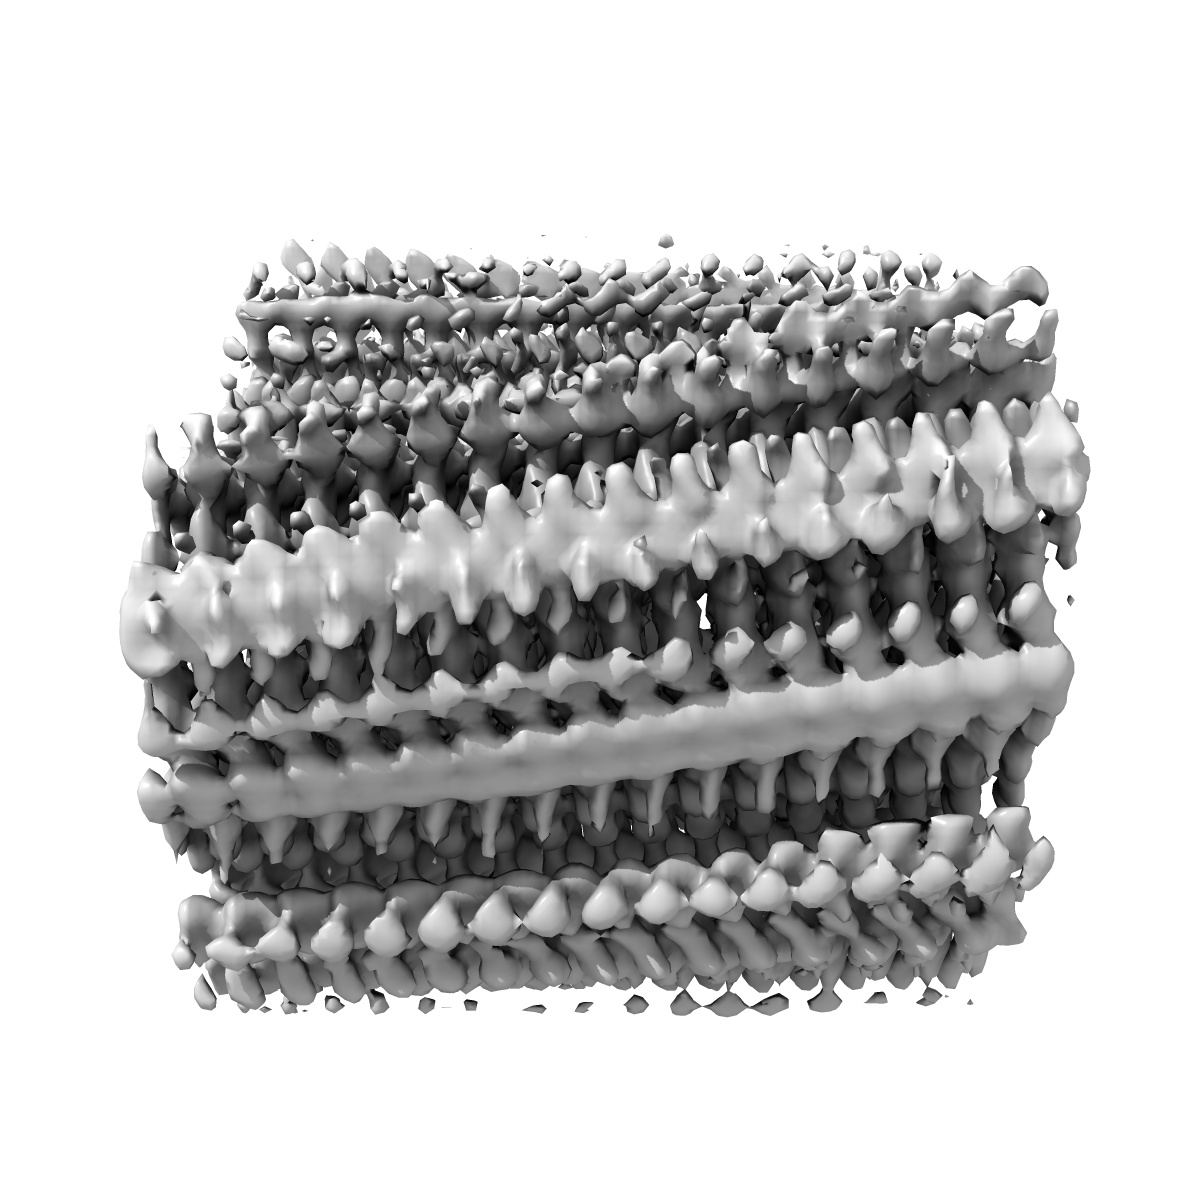

Additional cryo-EM structure of cardiac amyloid AL59 - bent polymorph

EMD-50271

Helical reconstruction3.9 Å